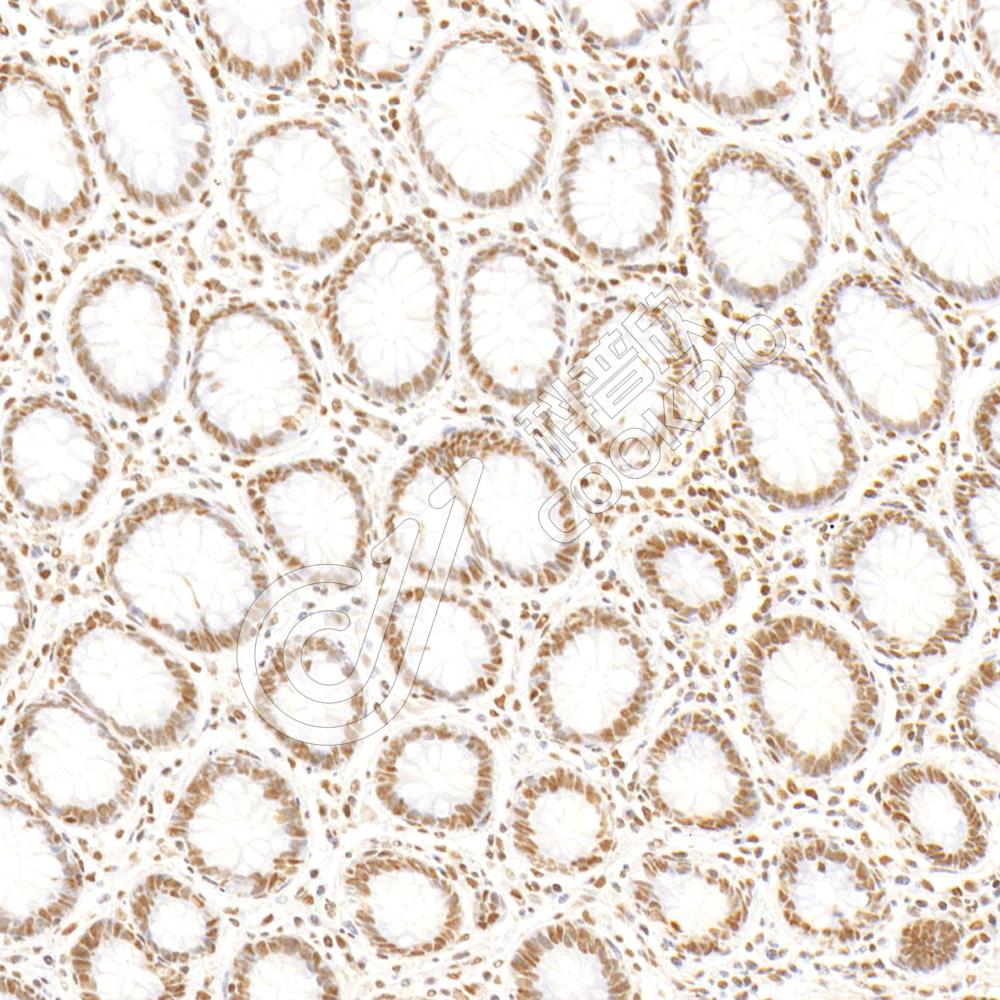

IHC检测METTL3蛋白(货号 K2374064).

样品: 人结肠癌, 4%多聚甲醛 (货号KSG1101) 固定12-24小时.

抗原修复: 柠檬酸抗原修复液(干粉, pH 6.0) (KSG1201), 高压锅均匀喷气计时2分钟.

—抗: 1: 800稀释, 4℃ 孵育过夜.

二抗: S-vision免疫组化多聚二抗(山羊抗小鼠), 即用型(货号KB3903), 室温孵育20分钟.